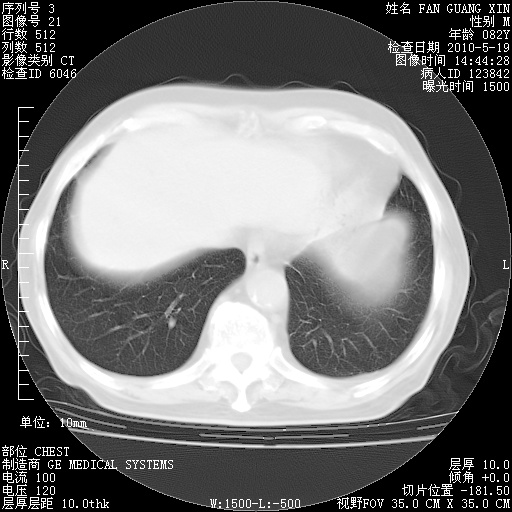

复查肺部CT,明显好转。为什么发热呢?

治疗3周后的肺部CT

治疗3周后的肺部CT纵隔窗